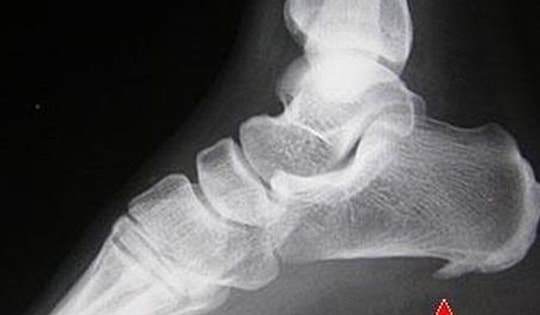

Các phương pháp điều trị gai xương và chăm sóc tại nhà

Gai xương là các cấu trúc xương nhẵn và cứng được hình thành ở cuối xương. Hầu hết các gai xương đều lành tính. Tuy nhiên, một số gai xương cũng có thể vỡ ra và bị kẹt bên trong các khe khớp gối. Các dị vật này có thể khóa chặt các khớp lại và gây khó khăn trong việc di chuyển.